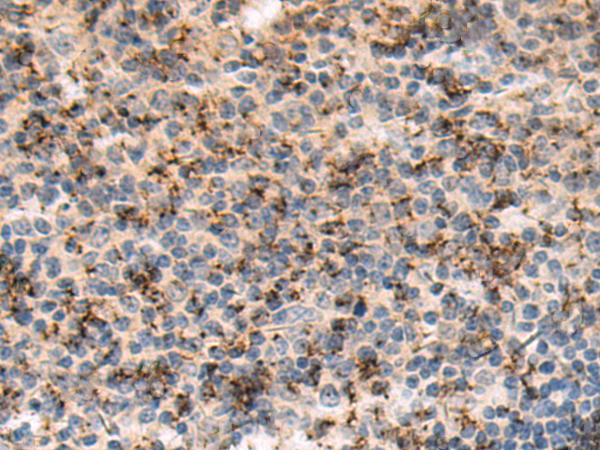

分类: 科研抗体货号: P10598别名: RCH2; SRP1; IPOA5; NPI-1应用: IHC反应种属: Human, Mouse, Rat